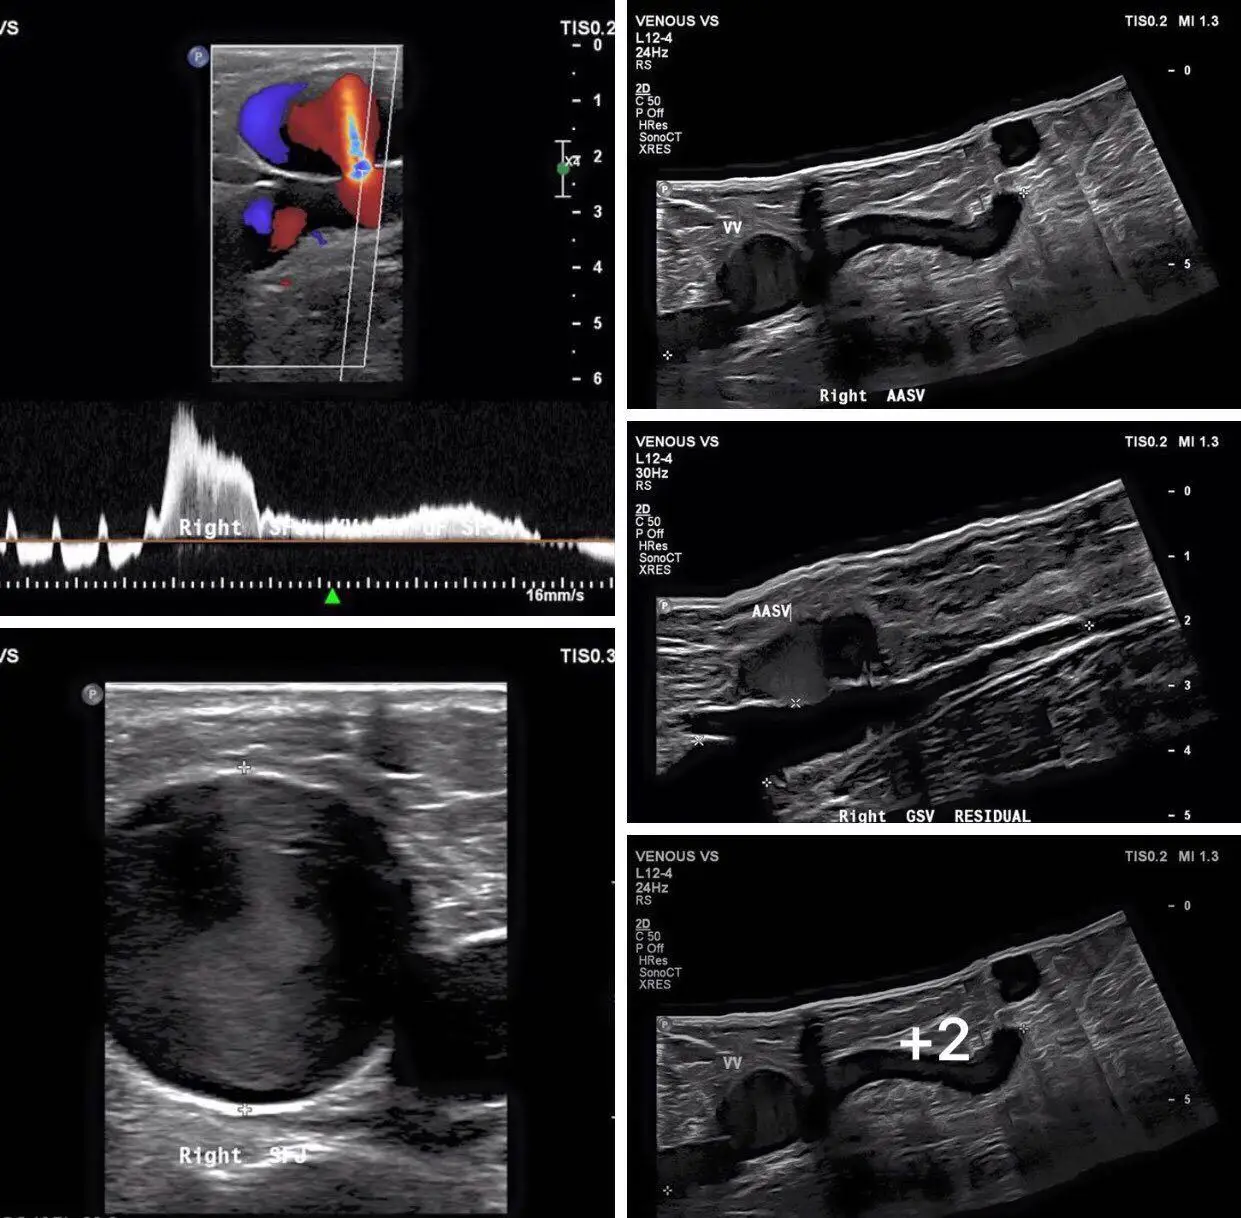

Color flow (CF), Power Doppler (PDI), Directional Power Doppler (DPDI)

Pulse Doppler (PW)

B+PW (Real Duplex),B+CF/PDI/DPDI+PW (Real Triplex)

distance, depth, area, circumference, volume, angle, stenosis ratio, ratio, speed, gradient (PG), acceleration, resistance index (RI), heart rate, velocity time integral (VTI), etc.

obstetrics, gynecology, abdomen, urinary, endocrine, blood vessel, heart, etc.

Scanning Images